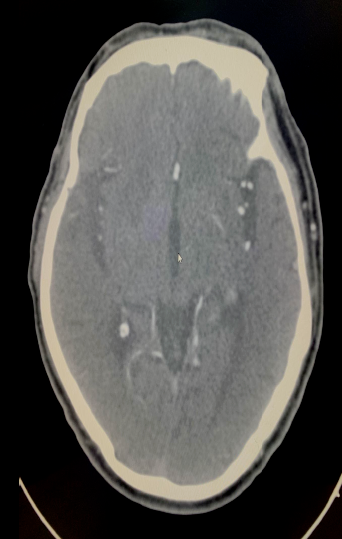

术后情况

• 术后治疗:

1.替罗非班24小时

2.停替罗非班前6小时桥接阿司匹林肠溶片、氯吡格雷

3.严格控制血压

4.连续3天双侧大脑中动脉TCD监测血流

• 术后24小时,左侧肢体肌力4级,凝视消失,NIHSS 6